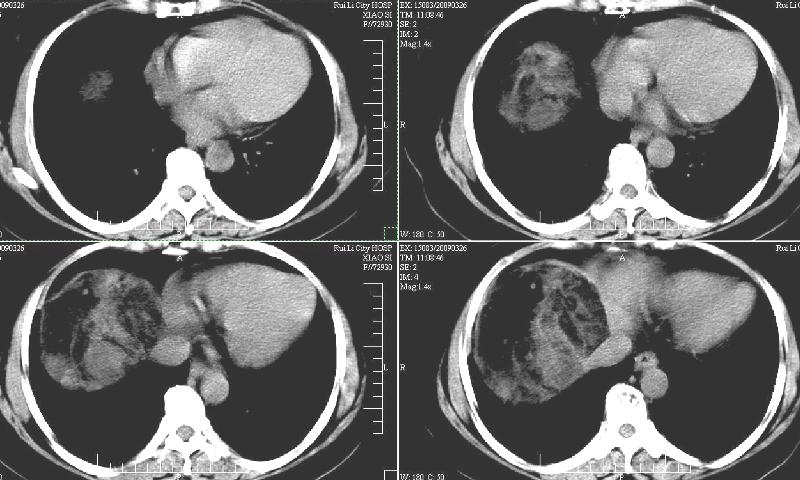

标题: CT19130:F,60岁。2008-10-17CT发现肝脏占位,现在复查! [打印本页]

标题: CT19130:F,60岁。2008-10-17CT发现肝脏占位,现在复查!

前次已经增强,所以这次没有增。ct:肝右叶平滑肌血管脂肪瘤治疗后复查,肿瘤大小同前或略有缩小。2、轻度脂肪肝。3、肝左叶小囊肿

支持楼主意见,肝右叶平滑肌血管脂肪瘤。